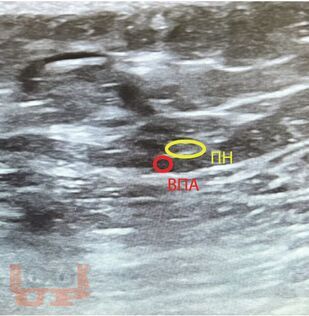

В учебном пособии отражены современные взгляды на одну из актуальных медицинских проблем - невропатию половых нервов. Авторами даны определение и классификация заболевания. Подробно рассмотрены мультидисциплинарные аспекты его патогенеза, диагностики и лечения. Представлены собственные результаты применения малоинвазивных хирургических методов лечения пациентов с невропатией половых нервов.